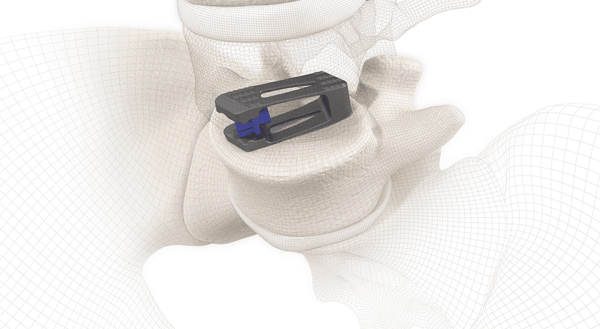

The next-gen TLIF implant is engineered to maximize performance in both traditional open procedures, as well as with endoscopic approaches.